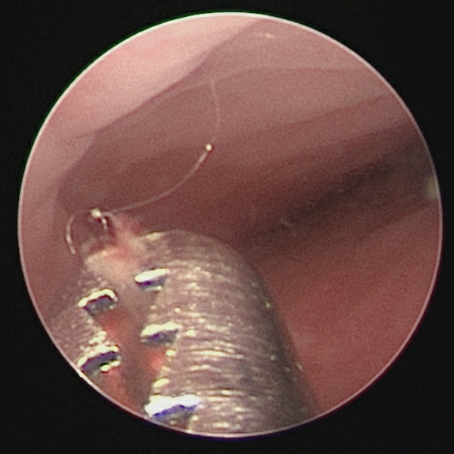

医生在阴道镜下用专门的工具(异物钳),小心翼翼将这团顽固的棉絮样异物完整地取了出来,并用碘伏溶液彻底冲洗了阴道。

医生正在用异物钳取出棉花

再次用阴道镜观察确认:困扰玫玫一年多的“元凶”被彻底清除了!阴道内变得干干净净了,且对阴道壁及处女膜都未产生损伤。